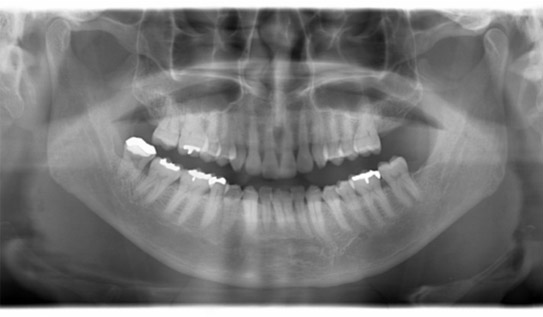

パノラマレントゲン写真